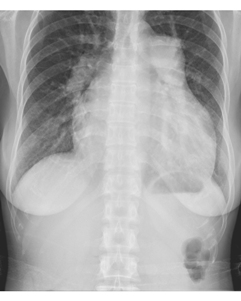

患者,女,33岁。心悸、气短,活动后明显。听诊胸骨左缘2~3肋间闻及收缩期杂音,肺动脉第二音亢进。胸部X线平片检查如下图:

5.该心型为

6.结合临床本病应考虑为下列哪种疾病

7.就该心型而言还应考虑下列哪些疾病

8.若要明确诊断最简单易行的检查方法是

9.该病的典型听诊表现为

10.该病合并下列哪种疾病构成Lutembacher综合征

正确答案:5.C;6.A;7.D;8.B;9.AF;10.D